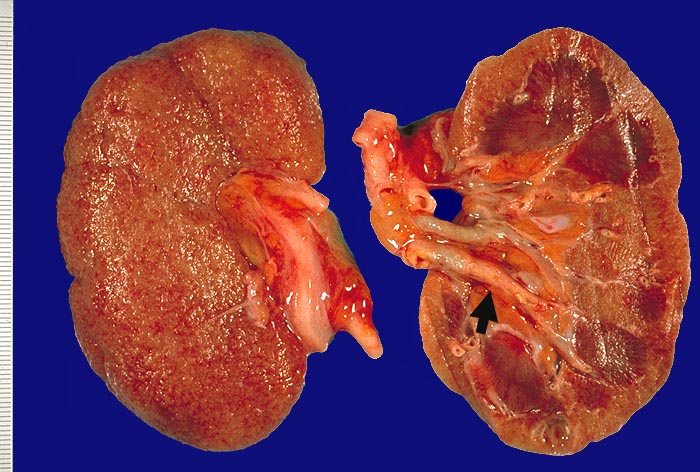

Im allgemeinen ist die Niere infolge von Glomerulumhypertrophie und Tubulushyperplasie vergrössert und derb, die Oberfläche ist granuliert. Bei schwerer Atherosklerose und fortgeschrittener Niereninsuffizienz kann die Niere auch normal gross oder verkleinert sein. Die Kombination von nodulärer Glomerulosklerose, hyalinen Schlingenkappen (=Proteinthromben in den Glomerulumschlingen (> 1916)) oder Kapseltropfen (> 1907) und Arteriolosklerose in Vas afferens und efferens ist beweisend für eine diabetische Nephropathie. Jede einzelne Läsion für sich genommen ist aber unspezifisch. Eine noduläre Glomerulosklerose kann auch vorkommen bei membranoproliferativer Glomerulonephritis (> 2652), Leichtkettenglomerulopathie oder Amyloidose (> 2019). Der nodulären Glomerulosklerose geht bei Diabetikern eine diffuse Glomerulosklerose (> 1906) voraus. Dabei zeigen die glomerulären Basalmembranen und das Mesangium eine progrediente gleichförmige Verbreiterung. Bei der nodulären und diffusen Glomerulosklerose handelt es sich aber wahrscheinlich um zwei pathogenetisch unterschiedliche, sich überlagernde Krankheitsbilder. Typisch bei Diabetikern ist im Unterschied zur arteriellen Hypertonie die Arteriolosklerose von Vas afferens und efferens (> 1911) und oft auch der Vasa recta. Intrarenale Arterien können eine Atherosklerose mit Atheromen zeigen. Subendotheliale Proteinablagerungen teilweise mit Verschluss der Glomerulumschlingen (Schlingenkappen) und knotige Proteinablagerungen in der Bowman'schen Kapselbasalmebran (Kapseltropfen) gehören zu den sogenannten exsudativen Läsionen (> 1919) (> 1920) der diabetischen Nephropathie und führen zu Synechien sowie zur globalen Glomerulosklerose. Gleichzeitig mit den Glomerulumveränderungen treten tubuläre Basalmembranverbreiterungen auf, später eine Tubulusatrophie und interstitielle Fibrose mit Begleitentzündung. Auch die Basalmembranen der peritubulären Kapillaren sind verdickt.

Makroskopie

Befund

Pathologischer Befund